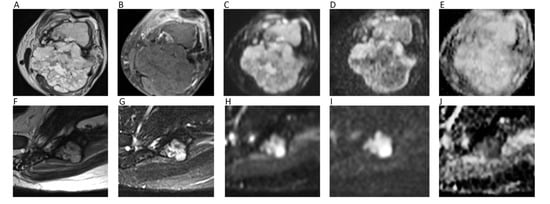

13. Bone Tumors

14. Soft Tissue Tumors

- Robba, T.; Chianca, V.; Albano, D.; Clementi, V.; Piana, R.; Linari, A.; Comandone, A.; Regis, G.; Stratta, M.; Faletti, C.; et al. Diffusion-weighted imaging for the cellularity assessment and matrix characterization of soft tissue tumour. Radiol. Med. 2017, 122, 871–879. [Google Scholar] [CrossRef]

- Subhawong, T.K.; Jacobs, M.A.; Fayad, L.M. Insights Into Quantitative Diffusion-Weighted MRI for Musculoskeletal Tumor Imaging. AJR Am. J. Roentgenol. 2014, 203, 560–572. [Google Scholar] [CrossRef]

- Choi, Y.J.; Lee, I.S.; Song, Y.S.; Il Kim, J.; Choi, K.-U.; Song, J.W. Diagnostic performance of diffusion-weighted (DWI) and dynamic contrast-enhanced (DCE) MRI for the differentiation of benign from malignant soft-tissue tumors. J. Magn. Reson. Imaging 2019, 50, 798–809. [Google Scholar] [CrossRef]